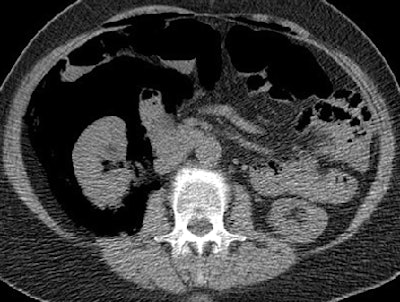

The second patient with perforation was a 70-year-old woman who had undergone screening colonoscopy. Acute angulation of the sigmoid colon prevented the colonoscope from being advanced more than 25 cm, and after five minutes of unsuccessful maneuvering it was removed. The patient had mild tenderness of the abdomen but no peritonism. She was admitted overnight and treated with antibiotics and IV fluids.

Overnight she developed worsening pain and a 38° C fever. "A diatrizoate meglumine and diatrizoate sodium solution enema examination the following morning showed no evidence of leak," they wrote. Symptoms resolved within 48 hours, and the patient was discharged from the hospital three days later with no further complications.

| Seventy-year-old woman who has undergone incomplete colonoscopy. Above and below: Axial CT scans of abdomen obtained before CT colonography show extensive retroperitoneal gas secondary to colonic perforation. Bottom image: Scout view from same examination shows extensive retroperitoneal air. All images courtesy of the American Roentgen Ray Society. Source: Hough DM, Kuntz MA, Fidler JL, et al. Detection of occult colonic perforation before CT colonography after incomplete colonoscopy: perforation rate and use of a low-dose diagnostic scan before CO2 insufflation. AJR. 2008;191:1077-1081. |